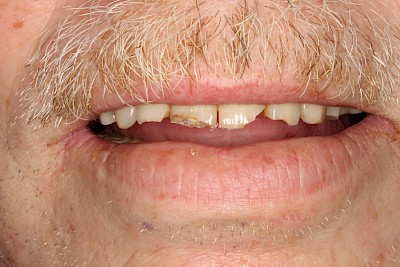

Absplitterung

Immer wieder kommt es vor, dass Zahnanteile oder auch Füllungen an Zahnecken teilweise oder ganz wegbrechen. Nicht immer haben die Betroffenen dann Zahnschmerzen. Trotzdem können scharfe Kanten an den Zähnen die Weichteile (Lippen, Wangen oder Zunge) verletzen.

Bei der Mundpflege und vor allem beim Blick in die Mundhöhle sollte besonders darauf geachtet werden, ob die Zähne vollständig sind. Wenn es ohne Biss-Gefahr möglich ist, sollte man die Oberflächen der Zähne auch mit dem Finger abfahren.

Verfärbungen und Abnutzungserscheinungen sind insgesamt eher unkritisch. Bei Absplitterungen bestehen häufig scharfe Kanten, die die Weichteile (Lippe, Wange, Zunge) in der unmittelbaren Umgebung verletzen können.